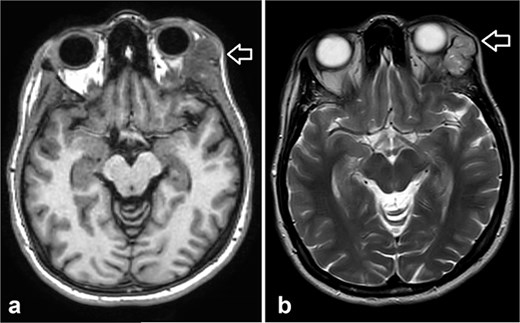

She was kept on follow-up for four years with clinical exams and MR imaging until she felt a palpable mass at the left lower dental root with local disease recurrence on orbit MRI (Fig. 3). An excisional biopsy from the submandibular mass revealed ACC, indicating metastatic disease. She was consequently given five cycles of paclitaxel and carboplatin chemotherapy.

Orbit MRI showed lobulated well-defined lesion, hyperintense to intermediate on T2W (a), hypointense on T1W (b) structures with cystic changes measuring 2 × 1.5 cm and 2 × 1.2 cm. After IV contrast administration they showed heterogeneous moderate enhancement.

MRI is the preferred modality to detect bony invasion and perineural spread. ACC usually appears as T1 isointense and T2 hyperintense with enhancement . Our patient's orbit MRI showed a lobulated, well-defined lesion, hyperintense to intermediate on T2W and hypointense on T1W structures with cystic changes.